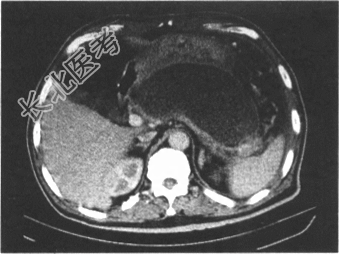

- 多项选择题5.患者入院治疗3周病情完全缓解后出院,1个月后复查CT见下图; 患者无明显不适主诉。目前应采取的治疗手段是

A、随访观察

B、开腹内引流

C、经皮穿刺置管引流

D、经胃镜下引流

E、ECRP+胰管支架

F、囊肿切除术

关注下方微信公众号,搜题查看答案